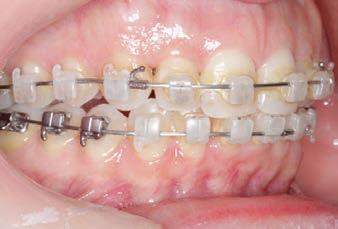

Carriere Motion 3D Appliance

Fastrack your orthodontic treatments. Save 6 months or more.

The SAGITTAL FIRST™ Philosophy is a time-tested approach that standardises, simplifies, and shortens Class II and Class III treatment times. It employs the Carriere Motion 3D Appliance to treat the AP dimension at the beginning of treatment before placing brackets or aligners. By resolving the most difficult part of treatment first, you can achieve a Class I platform in 3 to 6 months, shortening total treatment time by a minimum of 6 months1. You know how excited patients and parents become when you mention shorter treatment times.

CLASS II DIV.1 - Marra

PROVIDED BY: DR. LUIS CARRIÈRE

INITIAL - 4/4/18

PROGRESS 1 - 26/9/18 - Class I platform accomplished in 5.75 months with Motion 3D COLOR Appliance

PROGRESS 2 - 26/9/18 - Placement of the SLX 3D Clear Brackets

[CONTINUED ON NEXT PAGE]

with M-ONE .015 Cu Nitanium 27°

PROVIDED BY: DR. LUIS

PROGRESS 3 - 30/10/18 - With M-TWO .020 x .020 Cu Nitanium 35° archwire

PROGRESS 4 - 27/11/18 - 3 links power chain: 5, 4, bypass 3 to crimp hooks

PROGRESS 5 - 13/3/19 - With M-TWO .020 x .020 Cu Nitanium 35° archwire

PROGRESS 6 - 1/8/19 - With M-THREE.019 x .025 Beta Titanium wire

52 HENRY SCHEIN ORTHODONTICS

FINAL - 10/10/19 - Appliances removed AFTER

PROGRESS 7 - 10/10/19 - Final day in SLX 3D Clear Brackets BEFORE